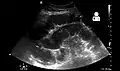

- Small bowel obstruction on ultrasound[19]

Radiological signs of bowel obstruction include bowel distension and the presence of multiple (more than six) gas-fluid levels on supine and erect abdominal radiographs. Ultrasounds may be as useful as CT scanning to make the diagnosis.[17]